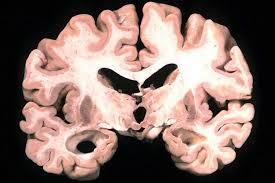

The Queensland Brain Institute in Australia has developed the highly promising treatment which works by clearing the brain of the neurotoxic amyloid plaques responsible for the loss of memory and other cognitive functions associated. The researchers applied ultrasound to mice with Alzheimers-like disease after injecting them with microbubbles that vibrate when they encounter ultrasound signals. The Queensland Brain Institute in Australia has developed the highly promising treatment which works by clearing the brain of the neurotoxic amyloid plaques responsible for the loss of memory and other cognitive functions associated. The blood-brain barrier is a network of blood vessels and tissues that stops. The current Phase 2 trial is the next phase to test the effectiveness of focused ultrasound as a treatment for Alzheimers. The treatment being tested known as focused ultrasound opens up the blood-brain barrier the semipermeable membrane that surrounds blood vessels in the brain. Ultrasound therapy improves the memory of Alzheimers patients. Götz wondered whether transiently breaching the walls using ultrasound might flush out soluble amyloid in Alzheimers-affected brains reducing the amount of. New Radiology Research Shows Promising Results for Focused Ultrasound Treatment of Alzheimers A new study by Rashi Mehta--a researcher with the WVU School of Medicine and Rockefeller Neuroscience Institute--finds that focused ultrasound may induce an immunological healing effect in the brains of Alzheimers patients.

The ability to noninvasively and reversibly open the blood-brain barrier in deep brain areas such as the hippocampus offers a new potential in developing treatments for Alzheimers disease The ultrasound targeted the hippocampus in particular because it plays a large role in learning and memory. The ability to noninvasively and reversibly open the blood-brain barrier in deep brain areas such as the hippocampus offers a new potential in developing treatments for Alzheimers disease The ultrasound targeted the hippocampus in particular because it plays a large role in learning and memory. For Alzheimers theres not that many treatments available despite hundreds of clinical trials over the past two decades and billions of dollars spent said Dr. New Radiology Research Shows Promising Results for Focused Ultrasound Treatment of Alzheimers A new study by Rashi Mehta--a researcher with the WVU School of Medicine and Rockefeller Neuroscience Institute--finds that focused ultrasound may induce an immunological healing effect in the brains of Alzheimers patients. Researchers find that using ultrasounds may help treat Alzheimers disease by opening the blood-brain barrier which blocks drugs from entering the brain. In a small group of patients language and memory showed improvement for up to 3 months after ultrasound brain stimulation therapy. Ultrasound therapy improves the memory of Alzheimers patients.